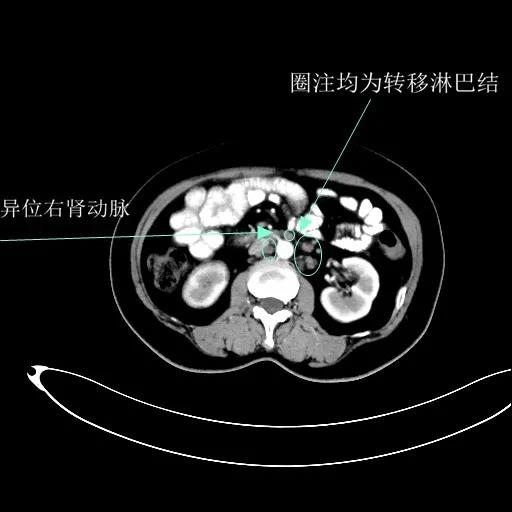

某患者因为“腹痛1周”而入院,外院B超提示子宫上方囊实性肿物,CT提示:左侧附件区占位,并盆腔及腹主动脉旁淋巴结转移。右肾动脉有右肾动脉及异位右肾动脉,其下均有肿大淋巴结。

排除禁忌后,在全麻下行“次广泛子宫切除+双附件切除+大网膜切除+阑尾切除术+盆腔淋巴结及腹主动脉旁淋巴结切除术”。术中切除腹主动脉左旁、右旁及后方淋巴结,达左右肾动静脉水平。多个淋巴结呈融合状态,长径约3-5cm。手术由陈亮副主任医师和宋趣清主治医师完成。

术后病理区域淋巴结状态如下:盆腔淋巴结(10/12)见转移;骶前淋巴结(2/2)见转移;腹主动脉左旁淋巴结(13/13)、下腔静脉前淋巴结(6/6)、肾静脉下淋巴结(5/5)、左、右肾动脉下淋巴结(6/6、1/1)见转移。